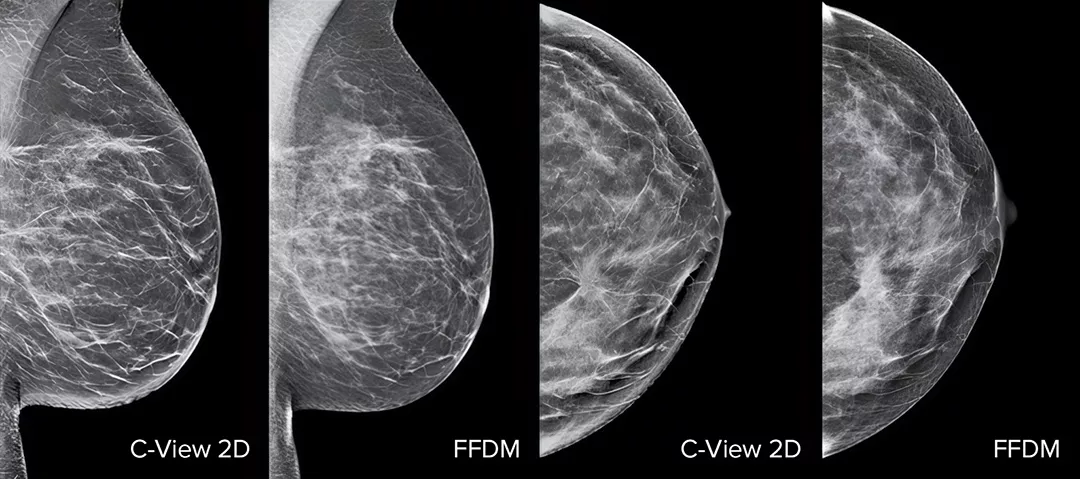

Architectural distortions, mass lesions, and bright spots commonly found in microcalcifications are more visible in the C-View 2D image than on the traditional FFDM 2D images or tomo slices.4,6-9

Architectural distortions, mass lesions, and bright spots commonly found in microcalcifications, are more visible in the C-View 2D image than on the traditional FFDM 2D image or tomo slice.4,6-9